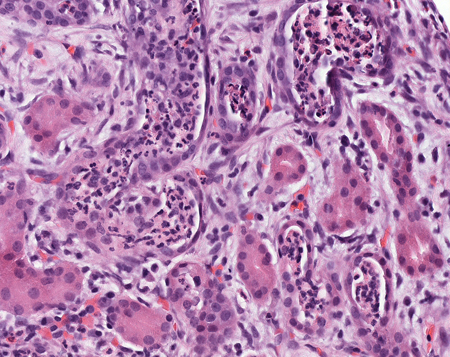

[Figure caption and citation for the preceding image starts]: Visualização de alta potência de células polimorfonucleares nos túbulos renais, que mostra danos aos túbulos e infiltrados de eritrócitos nos espaços intersticiaisCortesia do Dr. Jean L. Olson, MD, Departamento de Patologia, Universidade da Califórnia, San Francisco, EUA [Citation ends].